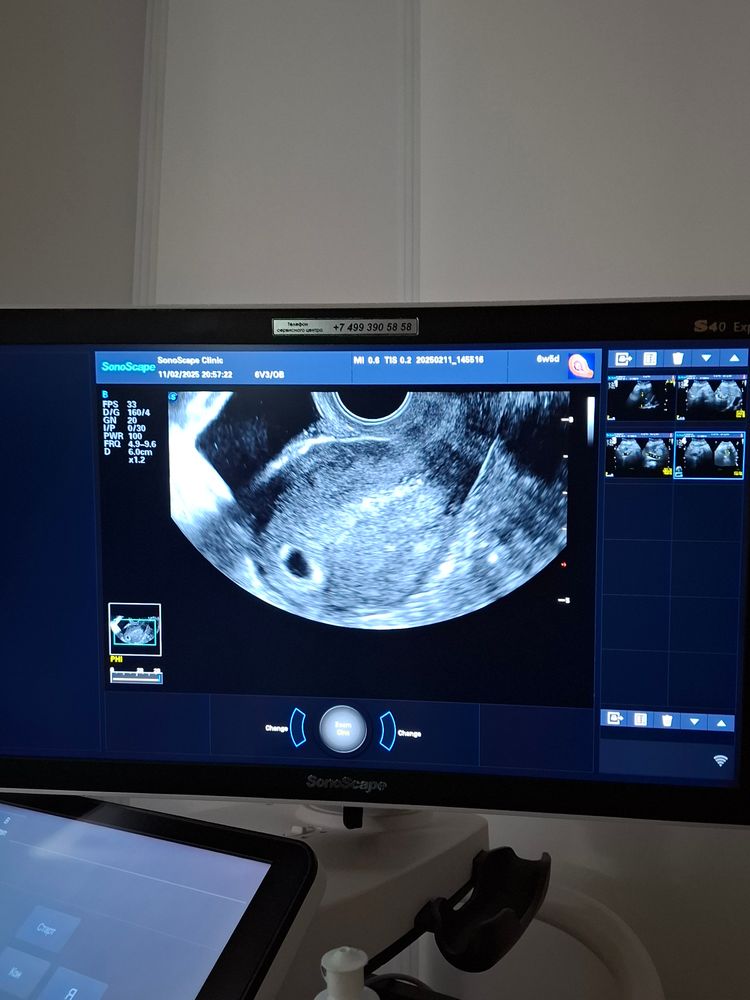

Первое узи, на душе легче не стало)))

Тоже вчера была на УЗИ, срок 5 недель и 3 дня, тоже не видят эмбриона,только ПЯ, сказали рано и записали на следующее УЗИ через 10 дней. Думаю, может даже позже перезаписаться, чтобы уже точно сердцебиение услышать, пока на 21 февраля( 6 недель и 6 дней будет- это от месячных 4 января) Овуляция была 18-19 января. Просто волнительно ожидание, но я уверена, ВСЁ БУДЕТ ХОРОШО! И у вас и у нас!

Видела ваш хгч в прошлом посте. У меня при хгч 3200 было только плодное яйцо чуть меньше 5 мм, даже желточного не было

Ирина, здравствуйте, спасибо за поддержку. Но мне кажется, это не от хгч зависит, а от дня цикла и тд. Потому что хгч может очень хорошо расти и при анэмбрионии тоже, это к сожалению не показатель. Важно,чтобы по срокам совпадало. А у меня разнос очень ощутимый

Руфина, не волнуйтесь, всё будет хорошо. У нас с вами примерно одинаковые сроки. Я в воскресенье была на Узи. Тоже эмбриона пока не видно. Но врач сказала, что на таком сроке это нормально. Через 2 недели, я уверена, всё будет🙏 и у Вас, и у нас🙏🫶

У вас же еще маленький ребенок. Месячные сначала нестабильные. На них бесполезно ориентироваться. А от вашей даты зачатия срок может быть меньше чуть ли не на 5 дней. Сегодня тоже была на узи и смотрю, что у нас в вами общего, иак это киста левого яичника))